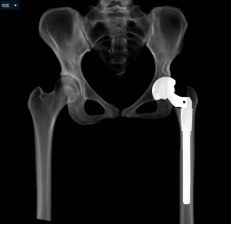

小张入院后,立即开始逐步进行相关检查,进行术前的准备。因为DDH的手术一般比较复杂,特别是这种脱位程度较高的患者,所以术前就需要更加精准的规划。对于小张的手术方法,耿硕制定了两套方案:一是如果原来真臼内及股骨头的软骨条件良好并且相匹配的话,那么可以尝试将股骨头放进髋臼里配合骨盆截骨重建髋关节;二是如果软骨条件不好或难以匹配,那么只能行全髋关节置换术。但是所有手术方案都会有一个挑战,就是如果在安装完髋臼杯及股骨假体后复位时把股骨下拉过多,可能会造成神经等软组织的牵拉伤并且因软组织张力过大可能造成假体松动,为了避免这种情况可能需要行股骨截骨减张,这样一期便不能恢复双下肢等长,需二期行骨延长术恢复下肢等长。在术前,为了适应软组织的张力状态及验证复位可能性,小张入院后即进行了患肢的牵引处置。为了精准的对手术做出规划,术前小张进行了下肢全长的三维CT扫描和模型重建,并且应用人工智能系统AI HIP对其进行术前手术方案的制定。人工智能能够利用患者的三维CT数据进行智能化识别解剖位点,匹配假体的大小及安放位置,通过对手术精准地预演,让外科医生在术前心中有数。通过人工智能系统的规划,计算出小张同学的双下肢腿长差和偏距差,计算出了旋转中心所需下移的距离和假体需要安放的位置等,髋关节置换方案为S-ROM假体系统,髋臼杯为PINNACLE 44号,内衬为BIOLOX28-44,因为患者比较年轻,所以选用了陶瓷对陶瓷的摩擦界面,能够实现更长的使用年限。根据术前规划数据,毕郑刚、耿硕团队提前准备了相应的假体和器械,为手术做了充分的准备。

(人工智能精准术前规划)